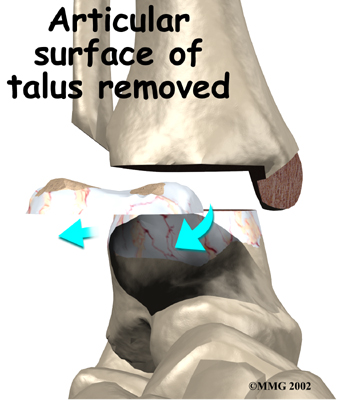

Several different operations have been developed to perform an ankle fusion. The basic procedure in each operation remains the same, however. The most common way that an ankle fusion is done is by making an incision through the skin to open the joint. Once the joint is opened, the surgeon uses a surgical saw to remove the articular cartilage surfaces of the ankle joint. Once the articular cartilage is removed on both sides of the joint, the body will try to heal the two surfaces together just as if it were fractured or broken.

Removing the articular surface of the talus